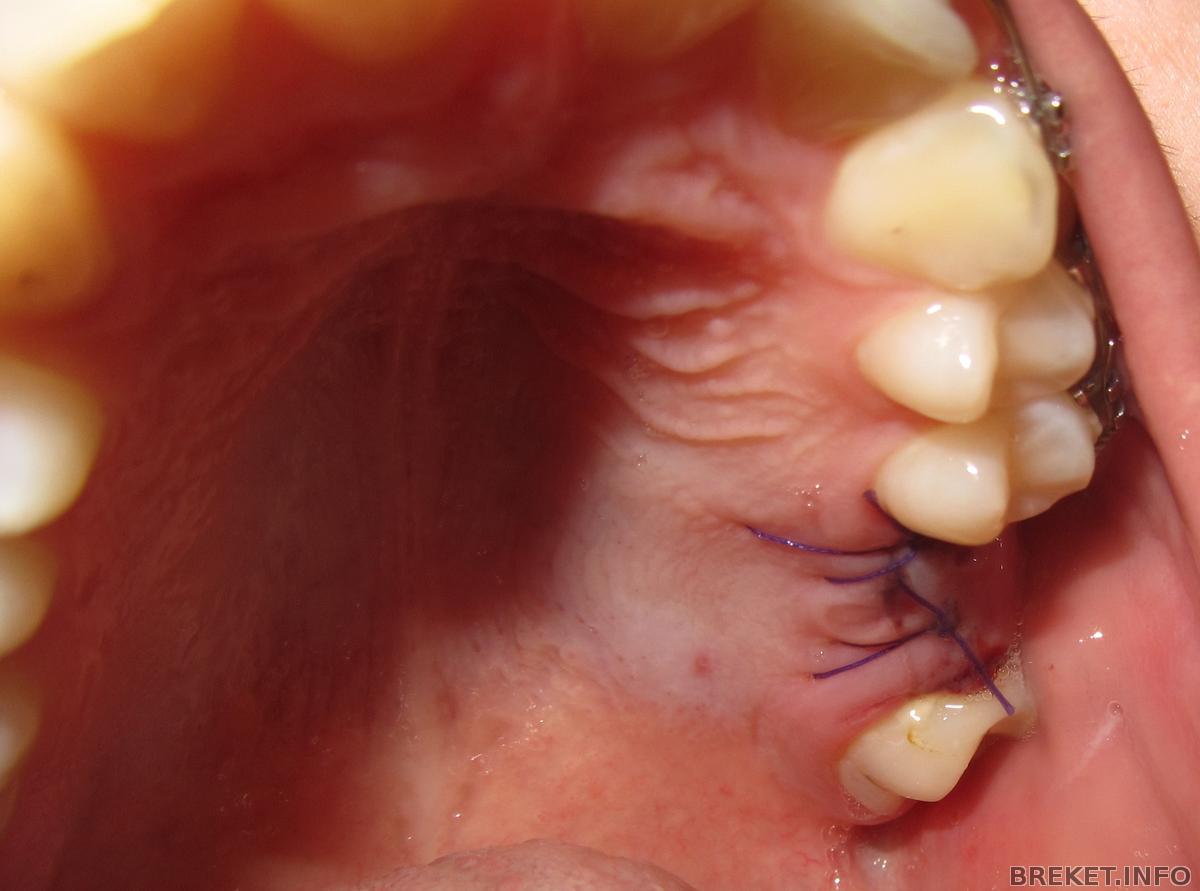

Операция длилась меньше 15 минут,вкололи антибиотик в попу,потом снимок, дали холод и рекомендации и отпустили. Выписали антибиотики 7 дней пропить. Перед едой мазать на шов смешивая метрагил дента и солкосерил дентально адгезивную пасту. После еды прополаскивать мирамистином. Еще сказали что кость очень мягкая и назначили пить кальций полгода...Начало болеть через час, я не стала терпеть и выпила обезболивающее. Поспала и сейчас ничего не болит. Перед установкой сдавала кровь на вич,сифилис, гепатиты, кальций, глюкозу и общий анализ крови. Вообще самое болезненное в операции это были уколы, даже слезы пошли. Имплантолога выбрала в той же клинике где и лечусь у ортодонта. Дугу мне скусили, всю не стали снимать. Записали на прием через неделю сделать контрольный снимок.

Спустя 1 день :

Добавлю что через неделю(27.10) сняли швы. Болело всего один вечер, потом неприятные ощущения доставляли лишь нитки. Пока без фото, всем удачи